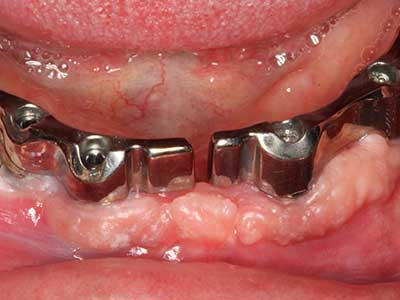

Bone tissue is not simply a mineral structure but also contains a substantial proportion of collagen fibres. This means it not only has good compressive strength but also a degree of flexibility, which can be taken advantage of when performing bone augmentations. In the classical expansion procedure using bone splitting, the atrophied alveolar ridge is split longitudinally and carefully expanded after reaching an adequate osteotomy depth (Fig. 13-16), ideally without substantial removal of the periosteum (Brugnami, Caiazzo et al. 2014, Stricker, Fleiner et al. 2014). Screw and plate systems with increasing expansion distance have proven effective in separating the two bone lamellae while remaining below the fracture threshold. In general, residual bone widths of at least 3–4 mm are required (Chiapasco, Zaniboni et al. 2006) to guarantee adequate flexibility and sufficient bone coverage of the future implants. If necessary, a vertical relief osteotomy on one or both sides can improve flexibility. A combination with additional augmentation techniques, particularly on the buccal side, has been described as an alternative to the classical technique.

The splitting procedure is particularly atraumatic and there is no significant loss of dimension when using piezosaws, and there are no significant differences between implants in split jaws and implants in an alveolar ridge without a bone deficit (Chiapasco, Zaniboni et al. 2006, Danza, Guidi et al. 2009). However, sufficient continuous irrigation is essential, particularly with locally restricted and deep splitting to prevent thermal stress in the apical osteotomy regions.